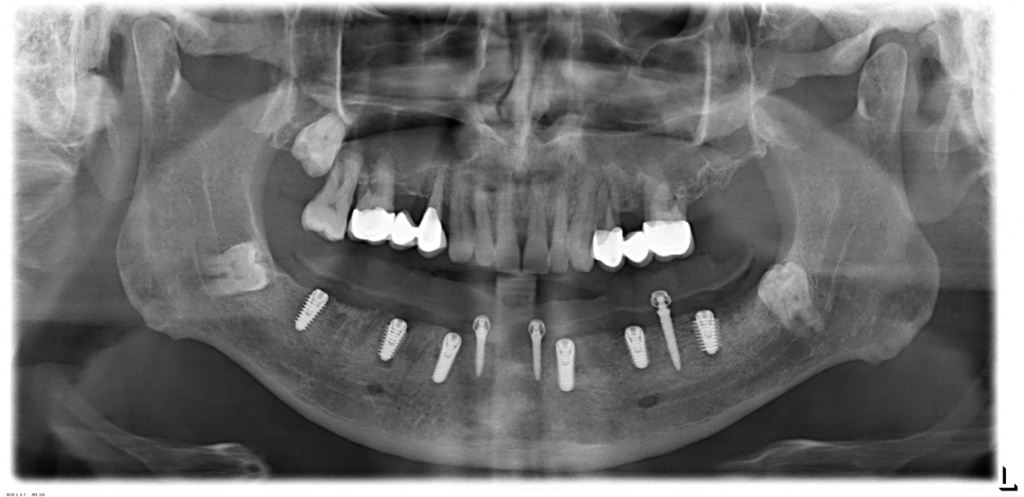

Ортопантомограммы пациентов до и сразу после имплантации. В 1-ом случае имплантат в позиции 36 и 27 , а на 2-ом снимке часть имплантатов установлены немедленно после удаления зубов.

CASE № 2

На нижней челюсти планируется установка условно-съемного протеза на балке. После протезирования на нижней челюсти планируется решение вопроса о протезировании на верхней челюсти (по настоянию пациента сроки раздвинуты).